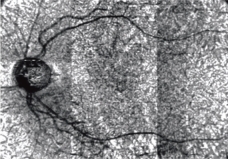

Multimodal imaging

RS-3000 Advance2とMP-3で解析された画像を組み合わせることでより詳細に病態を解釈し、診断に活用できます。

特徴のある部位(血管など)を2点以上指定することで、簡単にレジストレーション(重ね合わせ)画像を取得することが可能です。